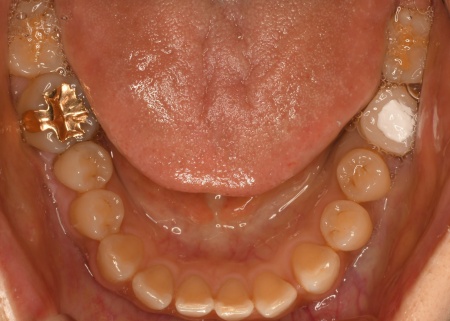

症例(精密むし歯治療)

50代女性 マイクロスコープを用いた精密な治療で歯の根に侵入した細菌を取り除きジルコニアクラウンで修復した症例

治療前

治療後

診療種別 自由診療

治療期間・回数の目安 6回(神経の治療は3回、歯の形を整える〜被せ物装着まで3回)

治療費総額の目安 ※記載の料金は治療当時のものです。

最新の治療費はお問い合わせください。

約410,000円

主なリスク まれに根管治療後も再治療、外科手術、抜歯などの処置が必要となる場合があります/治療中まれに器具の破折、被せ物や詰め物など修復物の損傷、歯の破折が起こる場合があります/治療中や治療後に不快症状が出たり、治療後に痛みや腫れなどが生じたりする可能性があります/装着に際し、天然歯を削る場合があります/硬い素材の場合、他の天然歯を傷つけることがあります/噛み合わせや歯ぎしりが強い場合、セラミックが割れる可能性があります